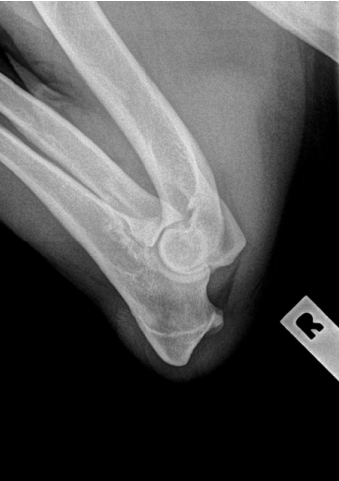

Elbows

- A single, fully flexed, medial to lateral view of each elbow is required, labelled L and R. This allows clear visualisation of the anconeal process, to check for any evidence of osteophyte formation.

- With the dog in lateral recumbency, the elbow to be radiographed is pulled away from the body, to prevent superimposition of the sternum, and then completely flexed. The chest is rolled away from the elbow, and the upper forelimb is pulled caudally.

- The x-ray beam is centred on the elbow joint, this can be achieved by palpating the humeral condyles and using them as landmarks for centring the beam.